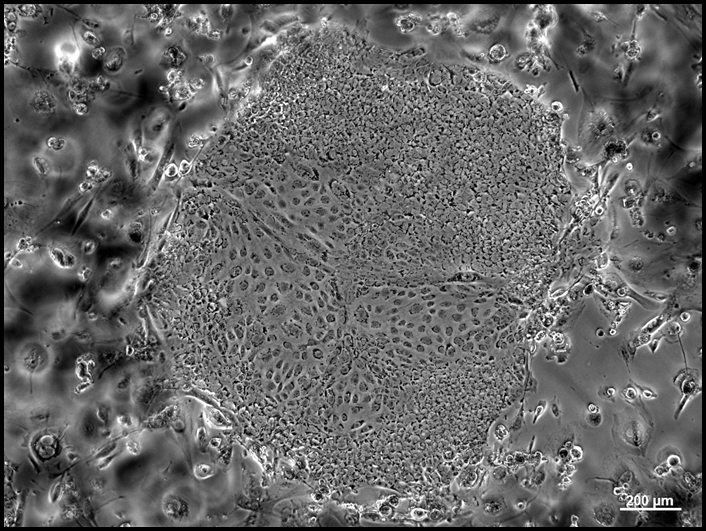

Rapid advances in stem cell and organ regeneration have put the biomanufacturing industry in a position of eminent uses. Stem cells therapies such as the treatment of macular degeneration are already in use and many more potential applications are currently in clinical trials at all phases. Lab grown organs, such as bladders, have been implanted in humans and advances in regeneration of other organ types are in development and animal trials today. The expansion of these products into human use has led to the need for training and skills in the application of stem cell technologies in an FDA regulated, current good manufacturing practice (cGMP) environment.

This workshop will introduce participants to the theory, concepts and practices of stem cell and organ regeneration in a cGMP environment. Workshop participants will conduct clean room gowning and advanced hands-on activities including the maintenance, transfer and differentiation of stem cells, and analytical methods to determine the success of directed differentiation. Additionally, guest lectures from industry experts and a tour of the Wake Forest Institute for Regenerative Medicine in Winston-Salem, NC will be included. Following the workshop, participants will be able to:

6.    Aseptically feed, transfer and treat stem cells for differentiation.